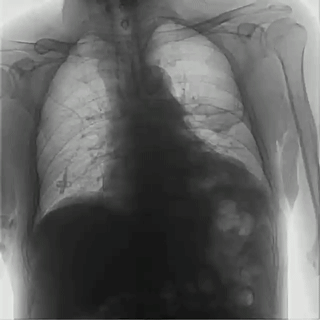

首先,具有可視化操作的功能,能通過多角度動態(tài)影像觀察,瞬時高清點片,更好地發(fā)現(xiàn)病灶并進行相關(guān)疾病的治療,解決了常規(guī)靜態(tài)DR不能解決的問題,減少漏診誤診,提高臨床診斷的精準性。

其次,臨床應用更加廣泛,能為影像科提供全科解決方案,針對體檢科、內(nèi)科、外科、骨科、急診科等也能提供相應的解決方案,且檢查更精準、直觀,擺位攝片效率極大地提升,大大節(jié)省拍片時間。

而且,影像采集幅面大,17×17英寸超大視野可覆蓋成年人的全胸全腹,并且能在連續(xù)動態(tài)中實時高清點片,從而達到精準診斷的目的。設備靈活高效的多維度運動設計,也帶來了更加智能化、人性化操作體驗,可大幅提升檢查效率。